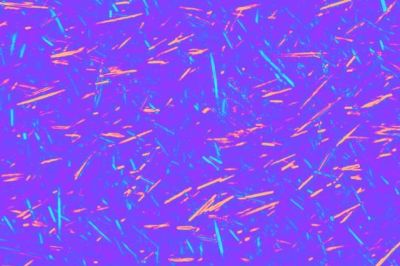

But the research team's platform, based on lens-free on-chip microscopy, can perform wide-field imaging without the need for lenses. It uses holographic imaging to produce high-resolution images of the crystal-like objects—the telltale signs of gout—in the patient's fluid sample.

The technology works by sending a stream of light through a polarizer, through a sample of the fluid on a microscope slide, and then through another polarizer before it reaches an image sensor microchip, a component also found in mobile phone cameras and webcams. The image sensor captures the holographic diffraction pattern produced by the sample and feeds it to a computer with software that can quickly generate an image of the sample. The platform can use the entire active area of the image sensor chip—about 20–30 mm2—allowing for rapid analysis of larger volume of samples. It also can be used at the point of care and in clinical settings with limited resources, Ozcan says.